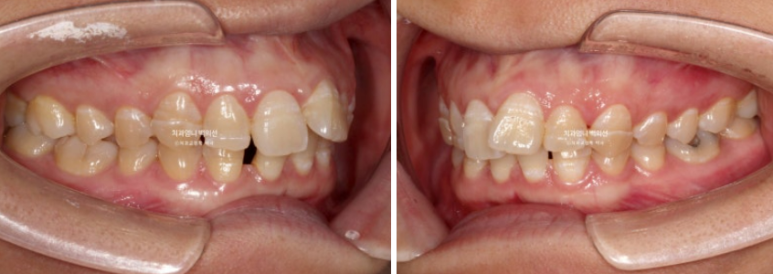

23년 10월 교정치료를 위해 찾아오신 30대 환자분입니다.

23.10

아래 앞니 사이에 벌어진 공간이 있고 위 앞니는 덧니가 있습니다.

앞니에 울퉁불퉁한 띠가 있는데 법랑질저형성증 입니다.

치아 건강에 문제가 되는 부분은 아니지만 오목한 부분에 음식이 잘 고입니다.

청결관리를 더 잘해줘야 합니다.

앞니가 튀어나와 돌출도 있습니다.

아래 앞니 4개 중 2개가 없습니다.

태어날때부터 없는 경우를 선천적 결손이라고 합니다.